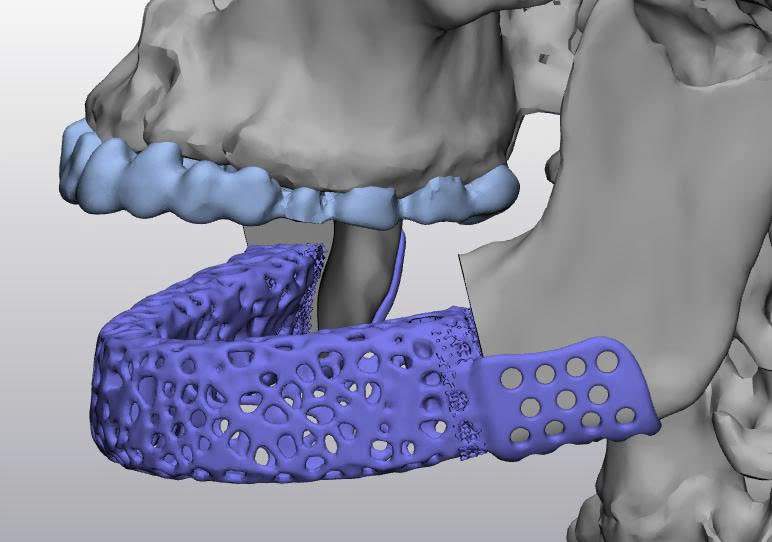

Hình ảnh trên minh họa quá trình thiết kế mô hình implant xương hàm dưới dựa trên dữ liệu CT-Scan. Các bác sĩ và kỹ sư sử dụng phần mềm chuyên dụng để:

Tái tạo cấu trúc xương 3D từ dữ liệu hình ảnh y khoa.

Thiết kế implant cá thể hóa: implant được tối ưu về hình dạng, độ dày, và lỗ thoát nhằm tăng cường sự tích hợp sinh học và lưu thông máu.

Mô phỏng phẫu thuật: cho phép bác sĩ xem trước kết quả phẫu thuật, giảm rủi ro và thời gian mổ.

Nhờ công nghệ in 3D, các mô hình implant được chế tạo với độ chính xác đến từng milimet, hỗ trợ phục hồi chức năng nhai và thẩm mỹ cho bệnh nhân sau phẫu thuật tái tạo xương hàm.